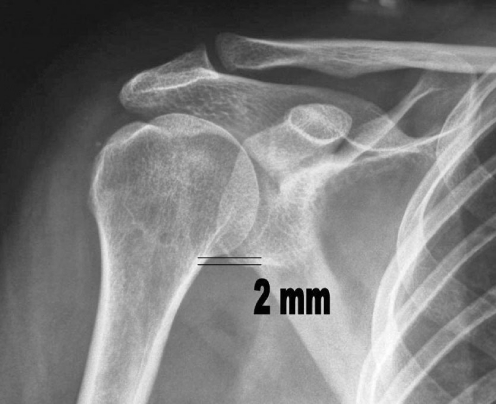

Fig. 2.

Postoperative radiograph showing depression of the humeral head after tendon transfer

Antero-posterior radiography of the shoulder, in neutral rotation, showed a mean proximal migration of the humeral head of 5 mm (range 1–7 mm); postoperatively, the mean proximal migration was 1.8 mm (range 0–4 mm) (P=0.001), a decrease of 3.2 mm.

Biomechanically, contraction of the deltoid due to loss of the supraspinatus muscle prompts a proximal migration of the humeral head, especially in the first few degrees of abduction, as shown by Burkhart [5] and Yamaguchi et al. [24]. The transferred latissimus dorsi, a powerful muscle innervated by the thoracodorsal nerve (C5–C6), becomes an external rotator for the shoulder, following the direction and mimicking the action of the infraspinatus. It also depresses the humeral head, increasing the deltoid lever arm, which might account for improved abduction and flexion of the shoulder joint. Depression of the humeral head occurs in the first place as a result of tenodesis, apparent here in the resting shoulder. However, Aoki et al. [2] report that the electromyography (EMG) examination of patients undergoing active physiotherapy confirms the contraction of the transferred tendon already apparent on palpation; this is likely to exert a further depressor effect on the humeral head, although the extent of depression was not tested here.